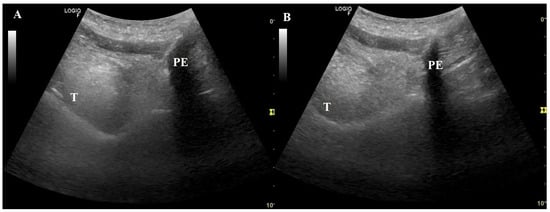

- Brekka, A.K.; Vollsæter, M.; Ntoumenopoulos, G.; Clemm, H.H.; Halvorsen, T.; Røksund, O.D.; Andersen, T.M. Adjustments of non-invasive ventilation and mechanically assisted cough by combining ultrasound imaging of the larynx with transnasal fibre-optic laryngoscopy: A protocol for an experimental study. BMJ Open 2022, 12, e059234. [Google Scholar] [PubMed]

- Andersen, T.; Sandnes, A.; Brekka, A.K.; Hilland, M.; Clemm, H.; Fondenes, O.; Tysnes, O.B.; Heimdal, J.H.; Halvorsen, T.; Vollsæter, M.; et al. Laryngeal response patterns influence the efficacy of mechanical assisted cough in amyotrophic lateral sclerosis. Thorax 2017, 72, 221–229. [Google Scholar] [PubMed]